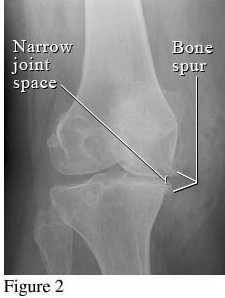

Hình ảnh so sánh giữa khớp bình thường và khớp bị thoái hóa khớp gối

Để phân biệt các giai đoạn của bệnh thoái hóa khớp gối, cần dựa vào phim X- quang theo tiêu chuẩn chẩn đoán thoái hoá khớp của Kellgren và Lawrence như sau:

2. Giai đoạn 2: Thoái hóa khớp gối độ 2

Hình ảnh của khớp gối trên phim X-quang: Khe khớp hẹp nhẹ, có gai xương nhỏ.

Giai đoạn 2 vẫn được xem là giai đoạn tiến triển nhẹ, xem trên phim X-quang có thể thấy kích thước bề mặt sụn khớp vẫn chưa có sự thay đổi nhiều. Bao hoạt dịch khớp vẫn hoạt động bình thường, cung cấp đủ dịch khớp để nuôi dưỡng sụn và bôi trơn ổ khớp, giúp các đầu xương hoạt động được trơn tru. Mặc dù vậy, bệnh nhân vẫn có thể xuất hiện một số triệu chứng như đau mỏi ở khớp gối sau khi vận động nhiều hoặc khi làm việc quá sức, làm việc sai tư thế; cứng khớp khi trời lạnh hoặc do ít vận động khớp.